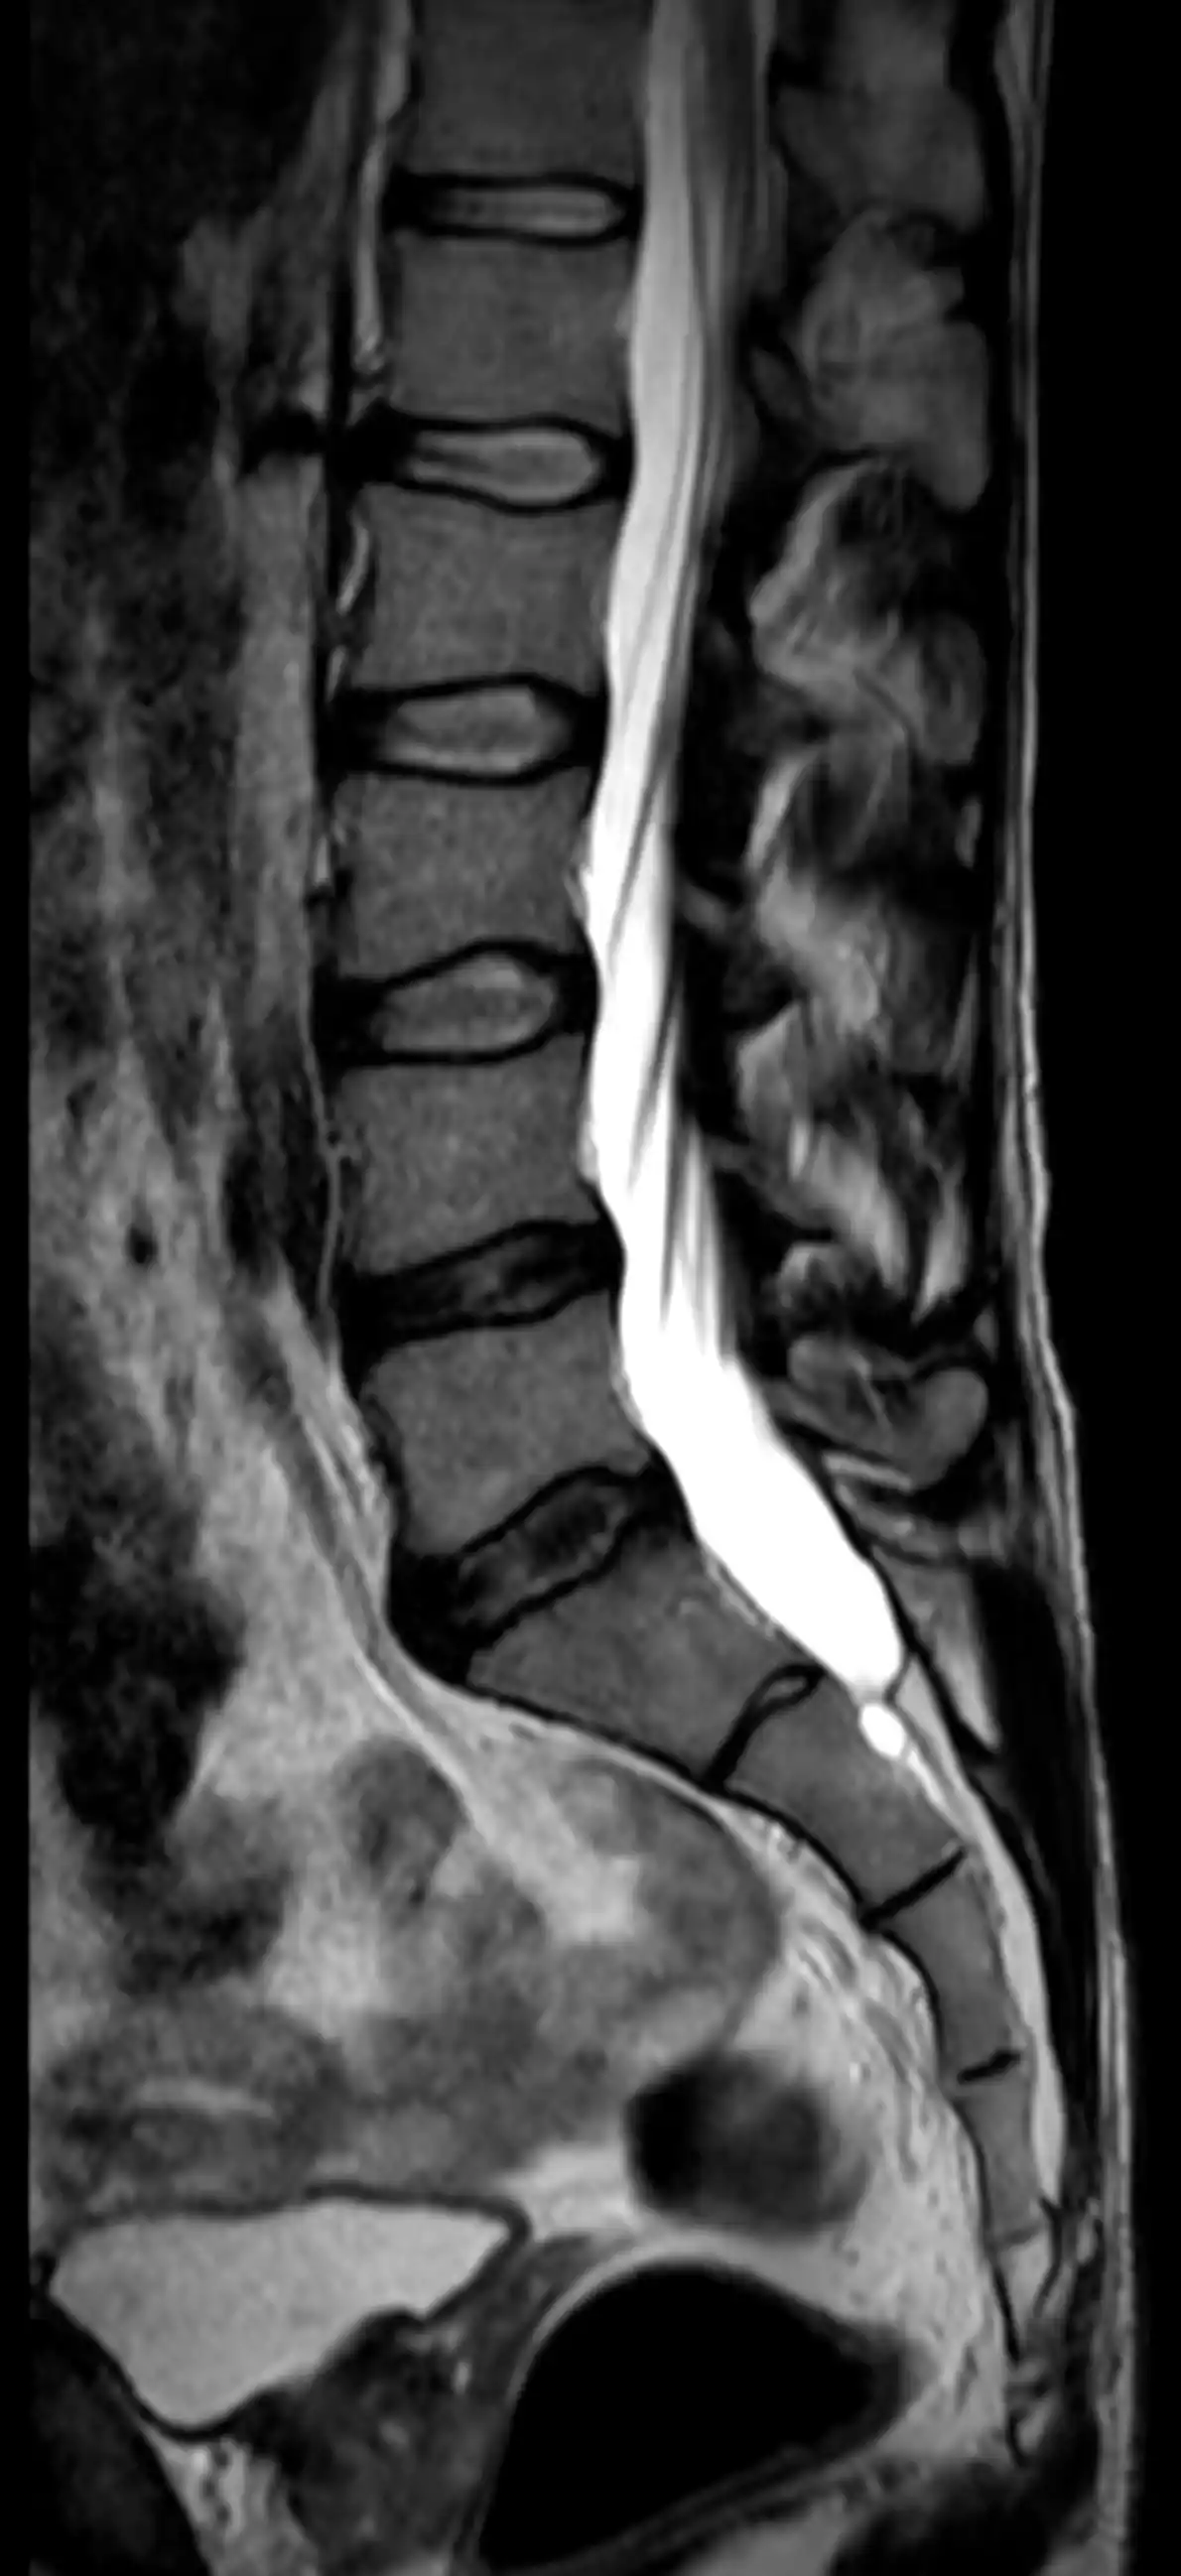

МРТ попереково-крижового відділу хребта — це сучасний метод обстеження, який дозволяє детально оцінити стан хребців, міжхребцевих дисків, спинного мозку, нервових корінців та м’яких тканин попереку.

Магнітно-резонансна томографія є одним із найточніших методів діагностики захворювань хребта і не використовує рентгенівського випромінювання.

- грижі міжхребцевих дисків

- протрузії дисків

- остеохондроз

- стеноз хребтового каналу

- защемлення нервових корінців